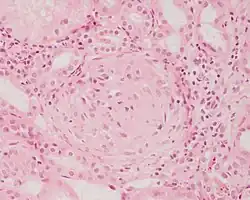

![]() | Dysgerminoma | Dysgerminoma characterized by uniform cells resembling primordial germ cells separated by fibrous septa with lymphocytes. | Category: Histopathology of ovarian dysgerminoma | Ovarian dysgerminoma |